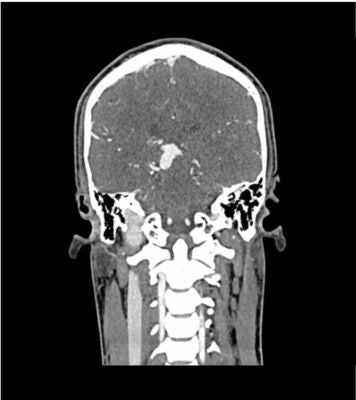

This phantom simulates a contrast medium-enhanced head in the arterial phase (CT angiography). It covers the vertex to the fifth cervical vertebra.

The phantom has 10 low-contrast lesions in the centrum semiovale and the right hemisphere has an arteriovenous malformation.

The phantom can be used in CT (including CBCT) to evaluate and optimize imaging performance and AI-enabled diagnosis. It is also suited for training purposes.

The phantom provides a detailed and realistic simulation of vascular structures, soft and bone tissue, including small details such as lymph nodes. Air voids are filled with a cellulose-polymer composite of approx. -160 HU.